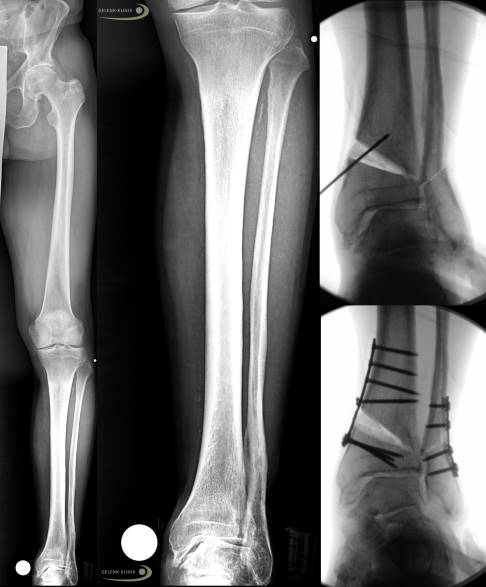

Operationen bei schweren Fußfehlstellungen

Schwere über Jahre entstandene Fehlstellungen oder Fußdeformierungen benötigen weitere korrigierende Operationen, die am Fersenbein oder auch an der Fußwurzel erfolgen können. Diese sind je nach Ausmaß zum Teil nur durch eine Versteifung mit Korrektur des Fußes realisierbar.

Eine Operation ohne Versteifung durch Verlagerung, Verdrehung oder Verkürzung am Fersenbein ist teilweise sinnvoll zur Veränderung der Stellung und der Fehlbelastung des Fußes.

Auch eine Stellungskorrektur am höchsten Punkt der Fehlstellung an der Fußwurzel kann eine sinnvolle Maßnahme sein. Diese Operation, bei der ein Fußkeil entfernt wird, ist gerade bei Fehlstellungen der Kleinzehen sehr effizient. Dabei wird ein Fußkeil aus dem Fußwurzelbereich entnommen und die Knochen danach wieder fixiert. Diese Korrektur ist neben vielen anderen Möglichkeiten eine sehr effektive Maßnahme, wenn nicht eine früher durchgeführte Behandlung die Fehlstellung verhindert. Je nach Ort der Fehlstellung kann die Position der Keilentnahme auch am 1. Mittelfußknochen im Rahmen einer sog. Tubby-Osteotomie oder am Fersenbein im Rahmen einer Calcaneusosteotomie oder Dwyer-Osteotomie sinnvoll sein. Die Wahl des Eingriffes kann zum Teil erst im Rahmen der Operation selbst erfolgen.

Vorgehen bei den beiden Operationen

Primär ist die schwere Fehlstellung im Sprunggelenk und damit die Fehlstellung des Rückfußes zu behandeln.

Beim 2. Eingriff wurde dann die Fehlstellung der Fußwurzel durch eine Keilresektion aus der Fußwurzel behoben. Die dadurch erreichte gerade Stellung des Fußes beim Stehen und Gehen ist hier besonders wichtig. Die Begradigung und damit die insgesamt bessere Belastung des noch vorhandenen Gelenkes im Fuß sind wichtige Ziele.